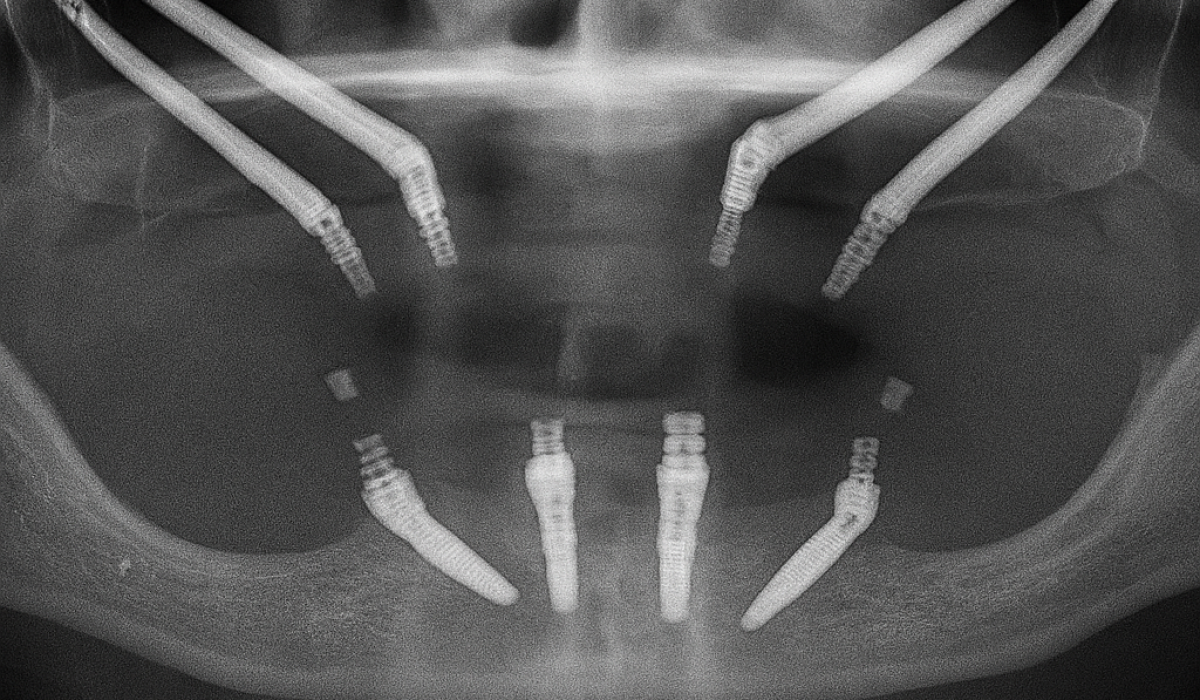

The main purpose of zygomatic implants is to offer a fixed, functional, and aesthetic prosthetic solution to a patient population that, until relatively recently, had very limited options. These patients, due to severe maxillary atrophy, are not viable candidates for the placement of conventional dental implants.

Zygomatic implants represent a cutting-edge solution in advanced oral implantology, designed specifically for the rehabilitation of patients with severe bone loss in the maxilla.

Uses native, dense bone The zygomatic bone provides strong cortical anchorage, creating an immovable base for long-span prosthetics, even after severe atrophy.